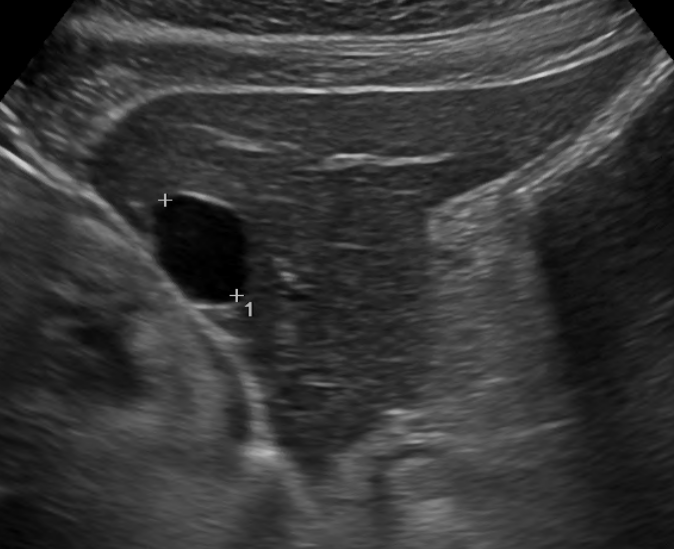

1) 초음파

가장 흔하게 사용되는 검사는 초음파로 간낭종 내부의 상태와 크기를 쉽게 확인할 수 있습니다. 검사 중에 방사선 노출의 위험이 없고, 쉽게 휴대할 수 있어 검진에 많이 사용되고 있습니다.